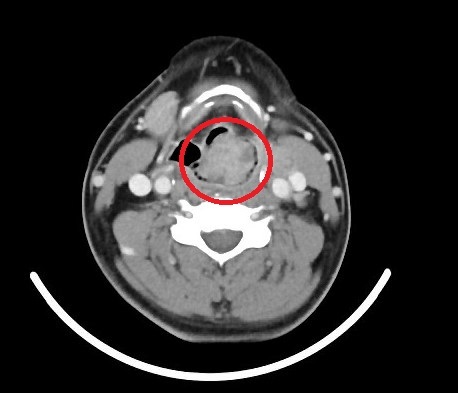

▲ 醫師提醒聲音沙啞可能是罹患肺癌、喉癌、下咽癌的警示(圖/澄清醫院提供)

澄清醫院癌症防治中心主任陳仁亮也呼籲,肺癌、喉癌、下咽癌、食道癌等癌症的發生,常與習慣性抽菸、喝酒、吃檳榔等不良嗜好有關。尤其是口、咽、喉部癌症,常見於40至60歲的男性。初期可能沒有明顯的症狀,有時等到有症狀已經是晚期。因此,除了不要輕忽沙啞等警訊外,定期健康檢查與癌症篩檢也是非常重要的。